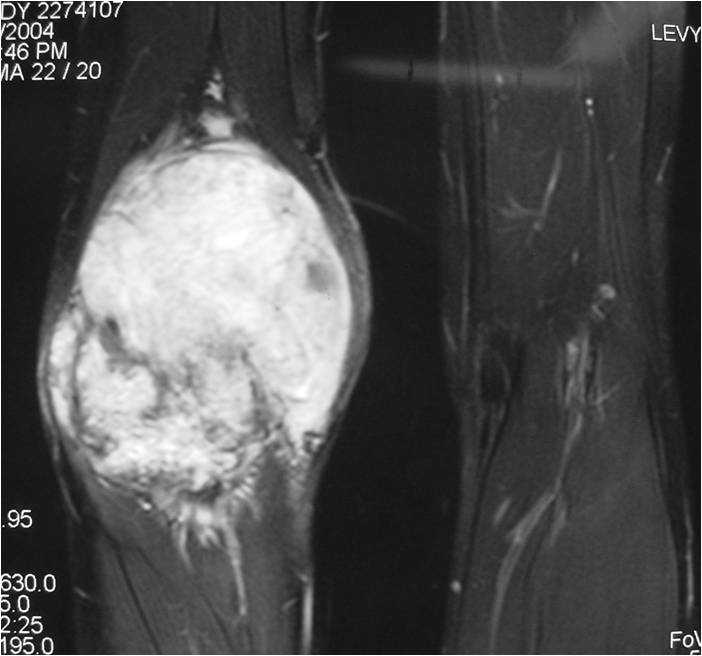

- Aggressive motheaten to permeative lesion

- Indistinct border in most cases

- Osseous destruction with a soft tissue component

- Chondroid matrix calcification may be present (60-70% of cases)

- Soft tissue mass